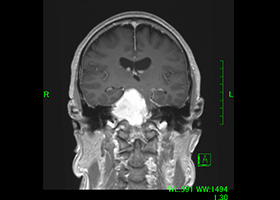

症例1)65歳男性、頭蓋底部巨大髄膜腫、外科手術のみ

[画像所見]

MRI造影検査で巨大脳腫瘍を認めます。

-

造影3DCT検査:錐体斜台部巨大髄膜腫認め

神経や血管を巻き込んでいます。 -

術前手術シュミレーション

術前 -

術後腫瘍は全摘出されました。